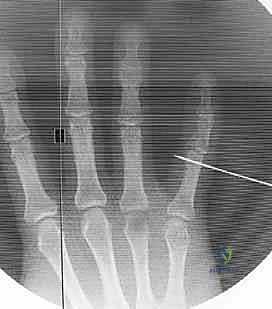

Fluoroscopic Confirmation (Partial Insertion): Insert the wire partially through the proximal phalanx, ensuring it crosses the head of the proximal phalanx. Immediately check its position with both true posteroanterior (PA) and lateral projections on the image intensifier.

Figure 1C (TECH FIG 1C) confirms the wire inserted across the head of the proximal phalanx, verified on the image intensifier, before further advancement.

Fluoroscopic Confirmation (Partial Insertion): Insert the wire partially through the middle phalanx and check its position carefully with both PA and lateral views on the image intensifier.

*Figures 1F and 1G (TECH FIG 1F,G) confirm the insertion and position of the distal wire on the image intens